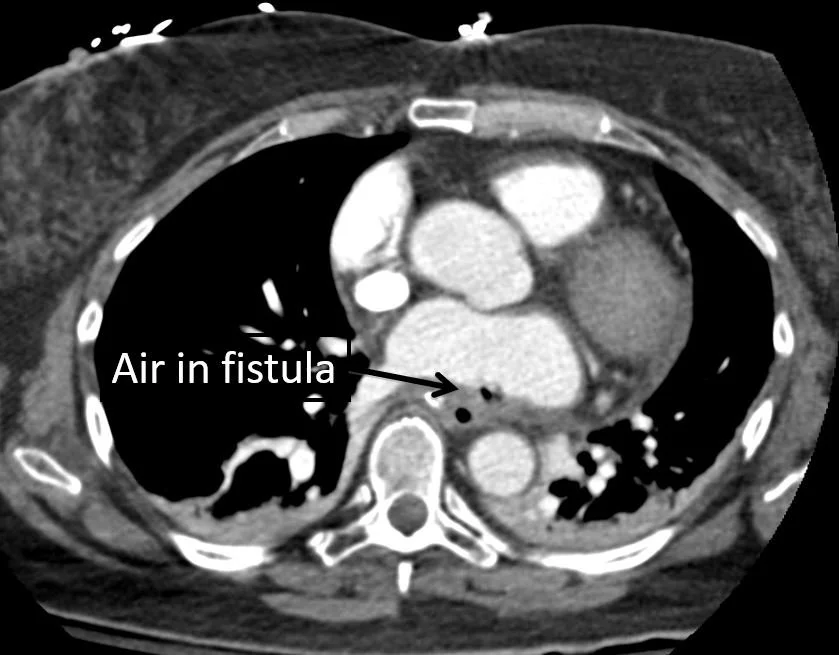

Our patient had an  atrio -esophageal fistula after his ablation and suffered an air embolus causing a stroke.

air was seen in the fistula

In the case of our patient an air embolus occurred through an atrio-esophageal fistula.  Other complications can occur as well: massive GI bleeding, pulmonary vein occlusion,  and sepsis.   It is recommended that an esophageal temperature probe be used as well an also occur as power reduction.